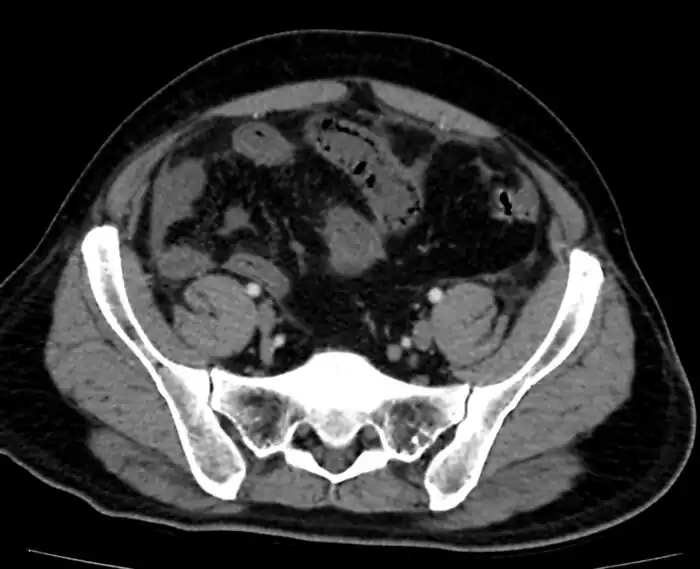

Mesenteric ischemia/CT image

Mesenteric ischemia